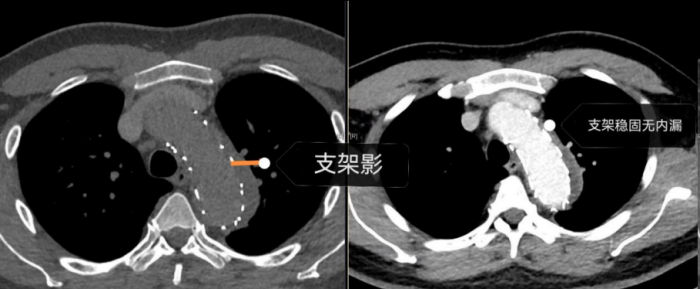

手术室内,患者血压一度飙至惊人的320/150mmHg,循环濒临崩溃!麻醉团队全力稳定循环。在患者下肢几乎无法触摸到脉搏的极端条件下,外周血管介入科主任赵扬程及团队迎难而上,凭借精湛技术,精准置入支架,成功封堵主动脉内膜巨大破口,并精细重建了主动脉弓部受累的重要分支血管,恢复关键血流。这场持续近3小时的手术每一步都高风险且高度紧张,如同在死神面前进行“拆弹”。最终,这颗“血管炸弹”被成功拆除。

术后,患者被迅速转入急诊重症监护室接受高级生命支持,重症团队24 小时严密监测,精准调控血压、凝血功能,防范并发症。几天后,患者病情稳定转入外周血管介入科病房,在医护人员精心治疗和护理下,闯过感染关、营养关、功能恢复关。8月15日,当患者朱宥安康复出院时,与妻子相拥而笑。随后,他的妻子紧紧握住医护人员的手:“谢谢你们救了我的爱人!救了我们这个家!” 这份沉甸甸的感激之情,是对所有参与救治的医护人员最大的褒奖。